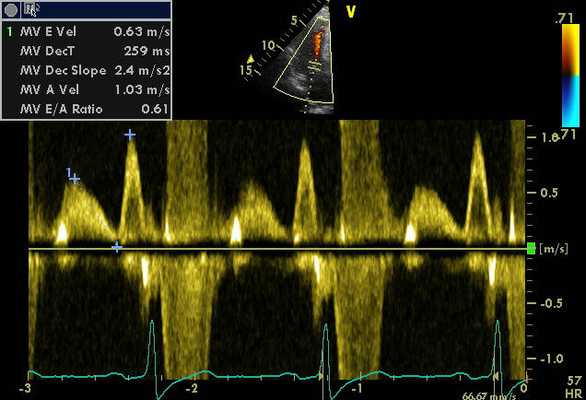

На сегодняшний день наиболее широко применяемым исследованием при помощи допплера является тканевая методика. Данный метод оптимизирован для изучения не только направления кровотока, но и визуализации движений сердечных тканей. В ходе допплеровского анализа происходит окрашивание миокарда в различные цвета в соответствии со скоростью и направленностью кровяного потока. Технику применяют для выявления локализованных изменений в сократительной функции миокарда. Данные, получаемые в ходе анализа, регистрируются в виде графика, отображающего зависимость скорости от времени.

Данные, полученные в ходе процедуры, являются важным диагностическим критерием, поэтому их расшифровкой должен заниматься высококвалифицированный кардиолог. В первую очередь специалист проводит оценку сократительной способности миокарда, а затем определяет параметры, функциональное состояние левого и правого желудочков.

Параметры работы сердца и движения кровотока в норме

При оценке данных проведенного скрининга у ребенка необходимо учитывать площадь поверхности тела.